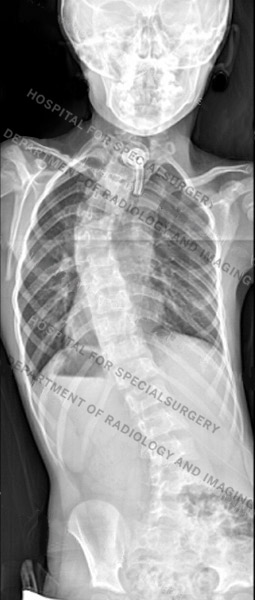

Posteroanterior (back-to-front) X-rays of dystrophic (first image) and nondystrophic scoliosis (second image)

The condition resembles adolescent idiopathic scoliosis, with similar types of curves and curve patterns.